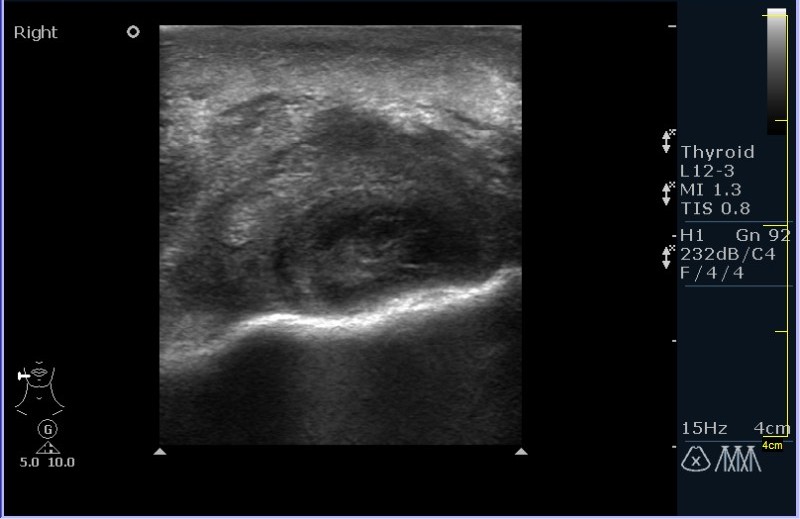

УЗИ области правой околоушной железы и угла нижней челюсти.

Девочка 8 лет, с опухлостью щеки и области правого угла нижней челюсти, резко боезненной при пальпации. В анамнезе (после наводящих вопросов :ugeek: ), визит к стоматологу около месяза назад.